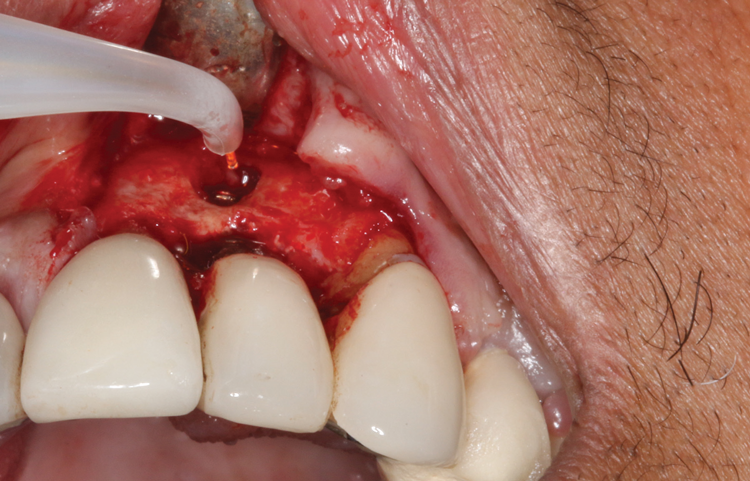

Following infiltration of the facial attached gingiva and palatal area with articaine hydrochloride 4% and epinephrine 1:100,000 (Septocaine®, Septodont [alternatively: Articadent®, Dentsply Sirona; Orabloc®, Pierrel]), an envelope releasing incision was made extending one full tooth over. To prevent trauma to the mucosal tissue, vertical incisions were not made (Figure 3). Incising the mucosa results in the release of prostaglandins and histamine, which increases postoperative discomfort. For this patient, staying in attached gingiva provided excellent control of the flap and allowed clear access to the apical lesion.

This is where the treatment became challenging. First, a curette was used to attempt to remove the granulation tissue from around the apex of the implant circumferentially. This was a difficult endeavor, especially on the palatal aspect of the site. Following curettage, an 810 nm diode laser (NV® PRO3, DenMat [alternatively: Picasso+, AMD Lasers; Gemini, Ultradent]) was used to treat the apical portion of the implant. After the laser tip was initiated using dark occlusal paper (Figure 4), it was used to debride the remaining necrotic tissue and decontaminate the entire site, reducing the bacterial count (Figure 5 and Figure 6).

(3.) An envelope reflection was made with no vertical incisions, exposing the entire bony defect affecting the apical portion of the stable implant.

Figure 3

(4.) The diode laser tip was initiated with dark blue occlusal paper.

Figure 4

(5.) The physical granulation tissue was ablated, and the entire site was decontaminated, reducing the bacterial count.

Figure 5

(6.) View of the cleaned site ready to be repaired.

Figure 6